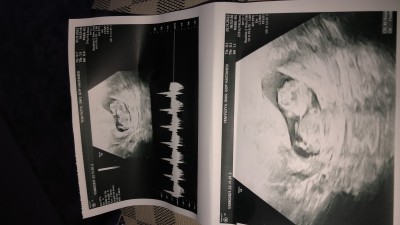

Tahminleri alabilir miyim hanımlar :)

Cinsiyeti hakkında ultrasondan anlayan varmı

Nedense erkek hissettim

Çok küçük ama kız gibi geldi

Popişini dönmüş kıza benziyor:)))

Erkek bence